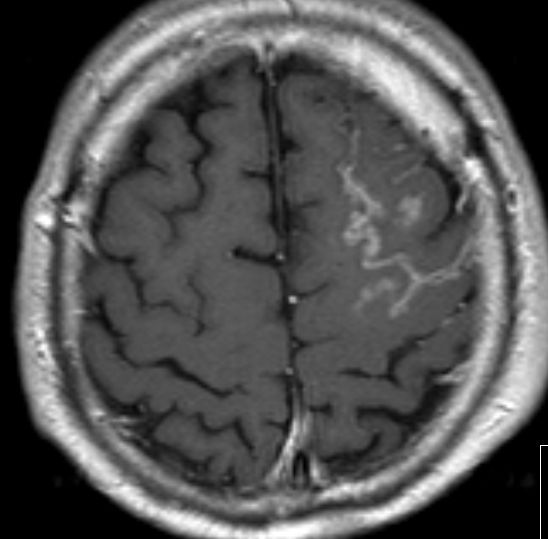

69-jähriger Mann 4 Monate nach primär metastasiertem Adenokarzinom des Ösophagus. Meningeosis carcinomatosa